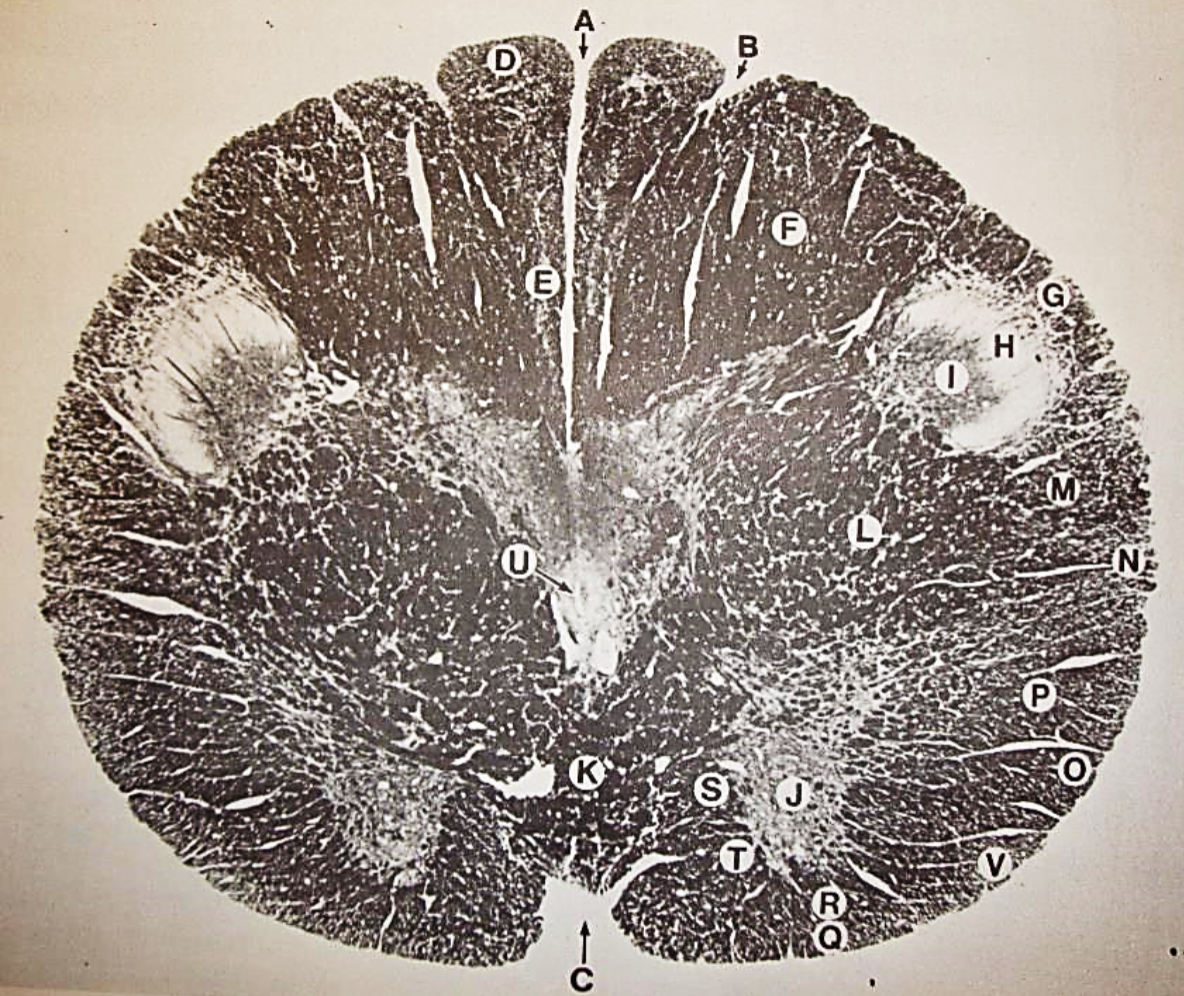

A

Fasciculus gracilis

B

gracile nucleus

C

fasciculus cuneatus

D

cuneate nucleus

E

spinal trigeminal tract

F+G collectively

spinal trigeminal nucleus

H

accessory nucleus

I

pyramidal decussation

J

rubrospinal tract

K

posterior spinocerebellar tract

L

anterior spinocerebellar tract

M

lateral spinothalamic tract

N

anterior spinothalamic tract

O

lateral vestibulospinal tract

P

medial longitudinal fasciculus

Q

tectospinal tract